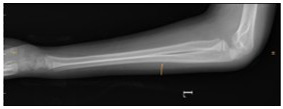

兒童的骨骼與成人堅硬的骨質相比,兒童骨骼較柔軟有彈性。因骨質尚未完全鈣化,較小的外力就可能造成骨骼彎曲或骨折。根據研究顯示,在18歲以前,約有50%的男孩與30%的女孩會經歷至少一次骨折。幸運的是,相較於成人骨折往往需3~6個月癒合,兒童通常僅需4~6週即可癒合,且石膏固定時間也大多在3~6週內,顯示出兒童骨骼強大的修復與塑形能力[圖一]。兒童骨骼骨膜較厚、含豐富膠原蛋白,這些都是促進癒合的有利條件。不過,兒童骨骼兩端存在尚未閉合的「生長板」,這是控制骨骼長度與形狀的重要部位。一旦生長板受損,可能造成骨骼彎曲、手腳長短或關節變形等後遺症。因此,若懷疑骨折波及生長板,需由專業醫師詳細評估與追蹤治療,以確保孩子未來的正常發育。

圖一 8歲男童左前臂尺橈骨折石膏復位治療一年後塑形結果